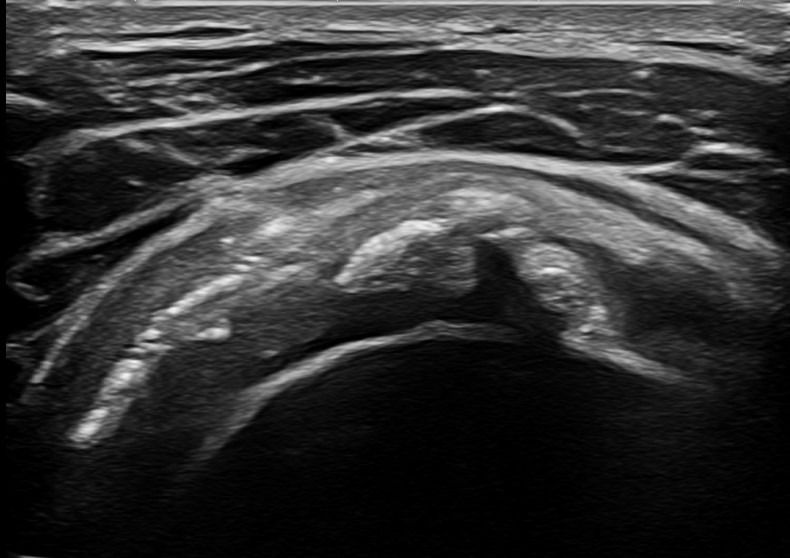

Σε περιπτώσεις Ρευματοειδούς Αρθρίτιδας ή Οστεοαρθρίτιδας το υπερηχογράφημα είναι εξαιρετικά σημαντικό για τη διάγνωση υμενίτιδας στην άρθρωση του ώμου.